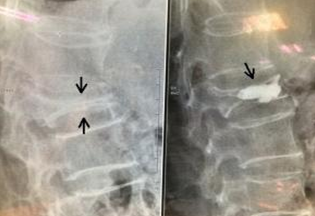

日前,我科接受一名脊柱压缩性骨折患者,患者已经88高龄,平时日常生活均能自理。由于在家如厕时不慎滑倒摔伤,患者既感到腰部疼痛,不能行走及翻身,经过检查,提示腰椎压缩性骨折,由于患者高龄,切基础疾病较多,能否手术成为了一个难题。

经过全面评估,我科主任认为只要合理控制基础疾病,患者可以进行手术。经过一系列周密的术前准备,主任对这位患者施行了微创经皮椎体后凸成形术。术后2天,腰部疼痛基本消失,患者即可离床行走,家属对这次治疗非常满意。